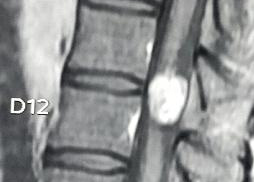

Intradural Neurofibroma